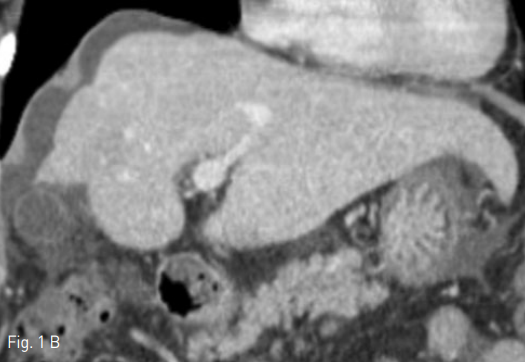

Fig 1B

Contrast enhanced CT scan showed features of chronic liver disease. Axial (A) and coronal (B) images showed hypertrophy of caudate lobe and lateral segments of left lobe with concomitant severe atrophy of the right lobe.

외부병원에서 시행한 컴퓨터 단층촬영(CT)검사에서, 간의 우엽은 심하게 위축되어 있었고 좌측외엽 및 미상엽은 증대되어 있어 만성간염에 합당한 소견이었다(Fig. 1). 이로 인하여 우측 간문맥 역시 매우 위축되어 있었으며, 우간정맥과 우측 간문맥의 거리가 멀어보였다.